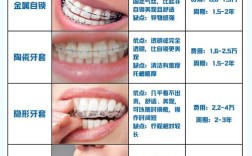

正畸拔牙是“以小博大”的科学决策,通过牺牲少量牙齿,换取口腔功能与美学的长期健康,医生会通过模型分析、X光片(头颅侧位片、曲面断层片)、面部测量等全面评估,结合患者年龄、生长发育阶段、主观需求制定个性化方案,面对正畸拔牙,无需过度恐惧,与医生充分沟通,理解拔牙的必要性和预期效果,才能更好地配合治疗,最终收获整齐的牙齿、稳定的咬合和自信的笑容。